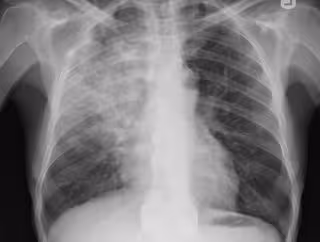

Neumonía, pulmonía, radiografía pulmones

FLICKR/YALE ROSEN - Archivo

Un equipo multidisciplinar del CIBER de Enfermedades Respiratorias (CIBERES) del Instituto de Salud Carlos III ha desarrollado un método de predicción de la agresividad de un tipo de neumonía con el objetivo de revelar si un paciente que llega a la sala de un hospital con síntomas de infección respiratoria desarrollará una forma agresiva de neumonía llamada distrés respiratorio o evolucionará a una forma de enfermedad mucho más leve.